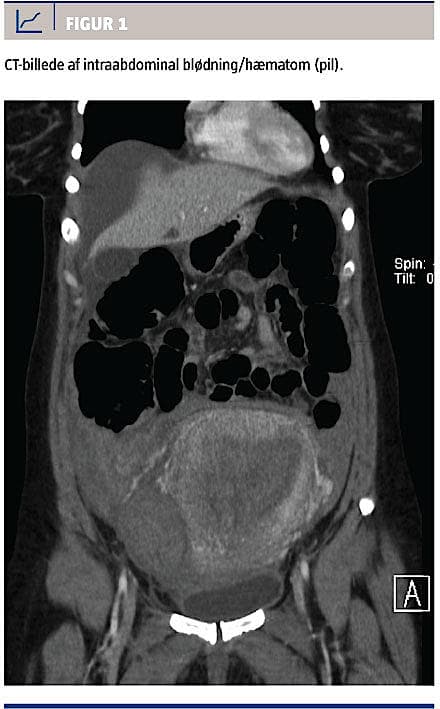

Tolv timer efter fødslen fik kvinden kraftige smerter fra epigastriet og diffust i nedre abdomen. Blodtrykket var 156/102 mmHg og pulsen 70 slag/min. Symptomerne blev tolket som efterveer, og tilstanden blev set an. Efter yderligere 12 timer blev den vagthavende læge tilkaldt pga. fortsat kraftige smerter. Kvinden var nu klinisk påvirket med et blodtryk på 80/50 mmHg og en puls 110 slag/min. En transabdominal ultralydskanning gav ikke mistanke om igangværende blødning, og mængden af vaginal blødning var tilladelig. Blodtrykket rettede sig hurtig med væskebehandling, men smerterne forværredes over de næste timer. Hæmoglobinniveauet var faldet fra 7,2 til 3,8 mmol/l. På mistanke om intraabdominal blødning blev der udført CT af abdomen, hvorved man fandt store mængder fri væske, specielt i højre side af abdomen, samt pleuraekssudat (Figur 1).

Der blev foretaget akut eksplorativ laparotomi, hvor man fandt et stort hæmatom i højre parametrium og blødning fra en sidegren af arteria uterina i højre side. Der blev opnået hæmostase ved ligering af det blødende kar, og det totale blodtab blev skønnet til seks liter. I efterforløbet blev kvinden behandlet for paralytisk ileus, pleuraekssudat og hypertension og rettede sig hurtigt. Mor og barn blev udskrevet i velbefindende til ambulant kontrol 14 dage efter fødslen.